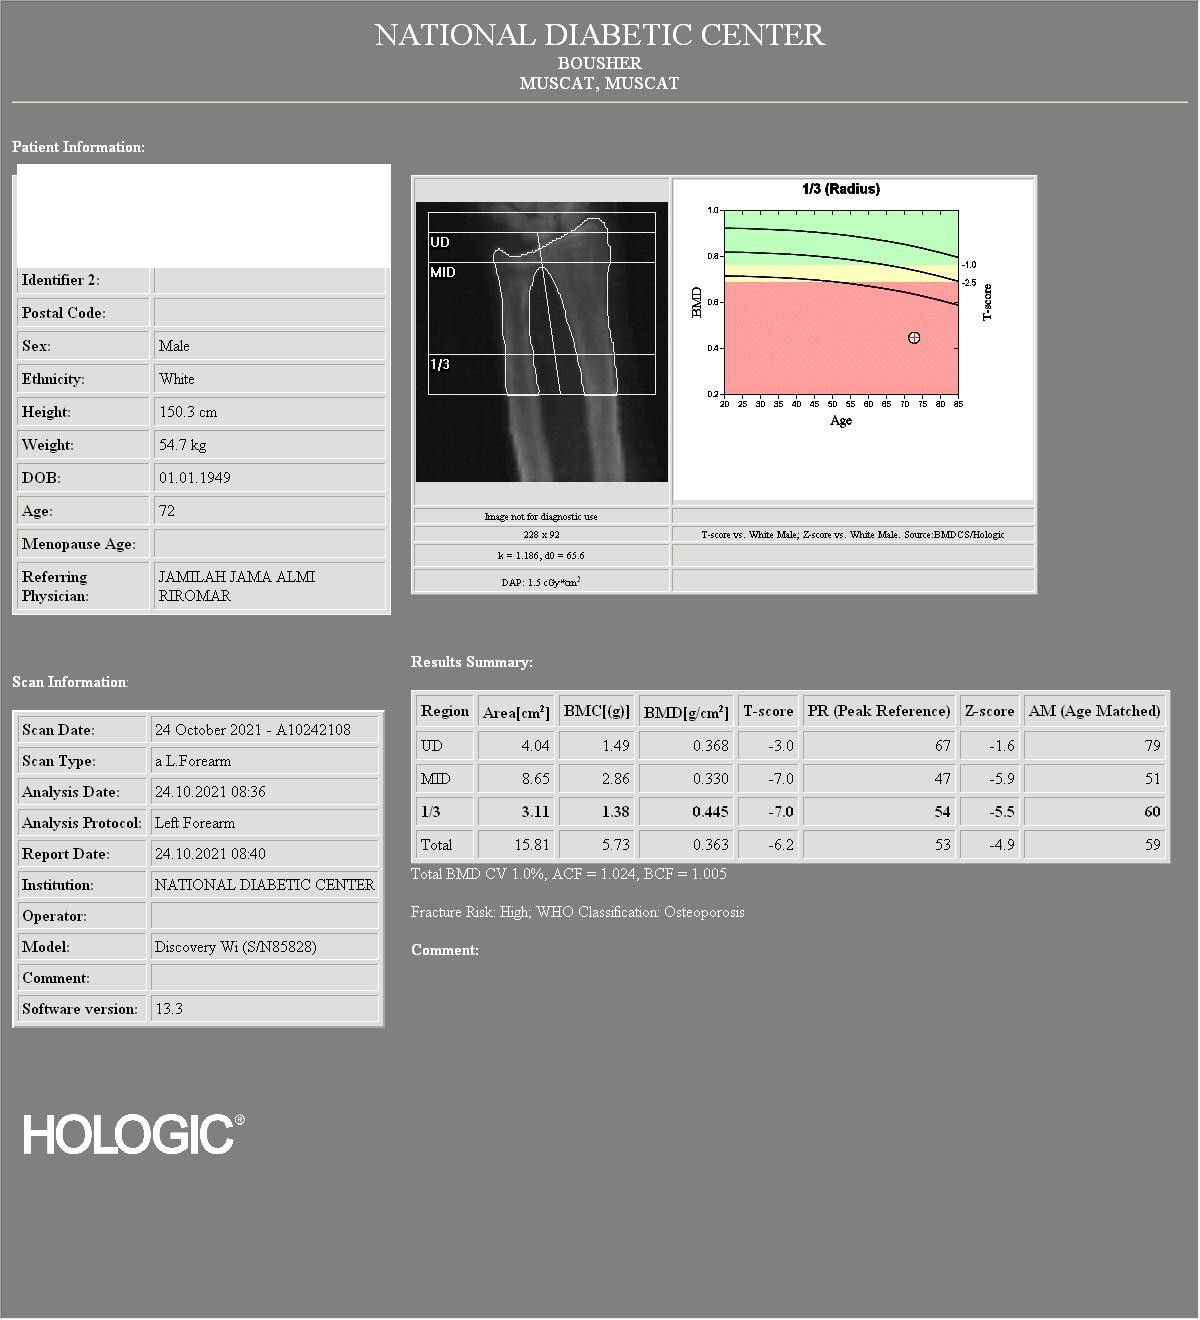

There is a black hole artifact over L4, therefore it was omitted from analysis. There are black hole-type artifacts over L4 and in the soft tissue.

This Hologic lumbar spine DXA scan shows a black hole-type artifact over L4. Items like lead bullets and tantalum clips show up as “black”on Hologic scans. The accompanying radiograph shows the clips over L4. L4 is omitted because of overlying artifacts.

Black hole artifacts occur with dense metals such as lead and tantalum on a Hologic scan. Other metals, like stainless steel, don’t produce black hole artifacts. Presumably there is complete attenuation of both Kev peaks so the difference is zero, making the image appear black. Lead bullets are measured as having high bone mineral content (BMC) and appear black in the dual-energy mode on the Hologic scanner and blue as artifact on GE Healthcare scanners. Black hole artifacts over bone are handled differently between Hologic and General Electric. With the Hologic scanner, when a dense artifact overlies bone, the BMC associated with that artifact is excluded, but the bone area is not altered. Consequently, the bone mineral density (BMD) of the affected vertebra, and of L1-4 is decreased. The GE scanners exclude both the associated BMC and area covered by the artifact, thereby minimizing the impact on BMD. Dense artifacts in the soft tissue do not significantly affect BMD on either manufacturer’s densitometer on phantom experiments., however, further experiments need to be done to verify this finding.